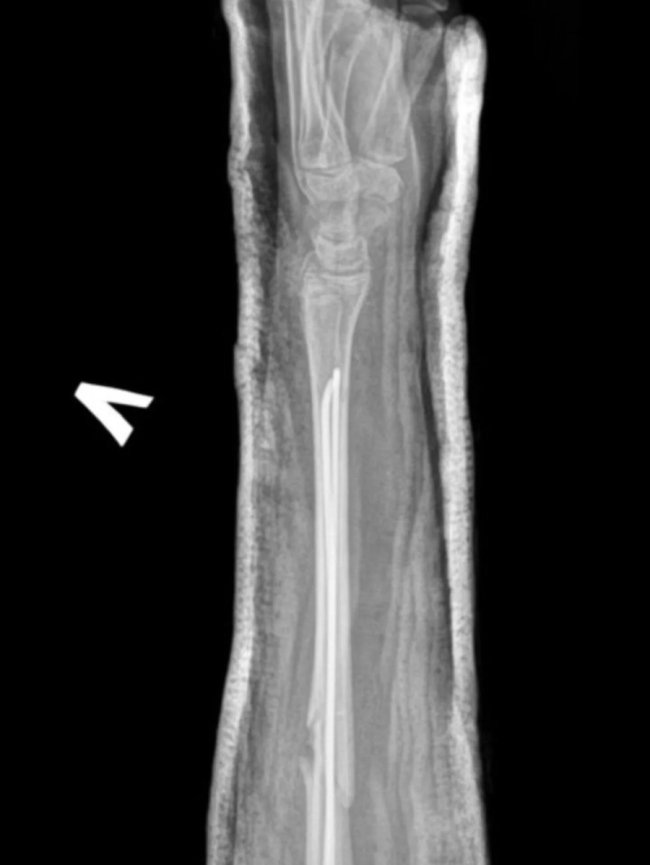

Ортопеди-травматологи Володимирського ТМО провели малоінвазивну операцію 14-річній дівчинці. Їй виконали закриту репозицію кісток лівого передпліччя з внутрішньокістковою фіксацією з ТЕНами.

Юній пацієнтці через два невеликі проколи шкіри передпліччя вправили зміщені уламки кістки без хірургічного розрізу, за допомогою спеціальних інструментів, відновлюючи правильне анатомічне положення кістки. Втручання проводилося під рентген-контролем.